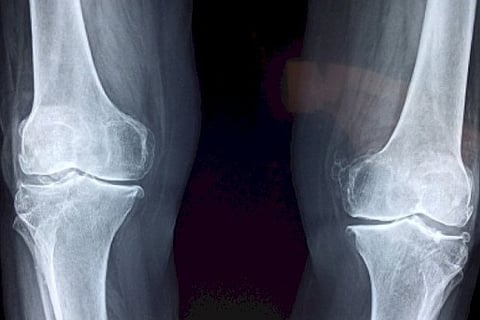

A team of doctors diagnosed the patient with advanced osteoarthritis with extreme varus deformity -- a condition in which the bone segment distal to a joint is angled inward, away from the body's midline. After the tests and all medical clearances, the team performed Bilateral Knee Surgery.

"The post-operation period was uneventful and now after almost a month, the patient is walking on his own, without any support and happily following his daily routine," said Dr Palash Gupta, Director & Coordinator, Department of Orthopaedics & Knee Replacement, at Max, in a statement TKR is mostly recommended for patients suffering from osteoarthritis, rheumatoid arthritis, post-traumatic arthritis, gouty arthritis, or those who have pain in the deformed knee.